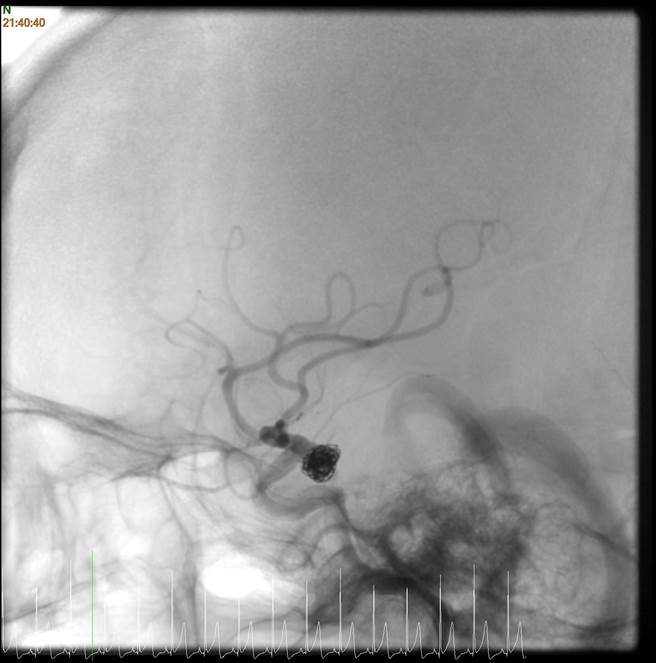

透过微细导管将白金线圈输送至动脉瘤内填满后,阻止血液再衝击脆弱的瘤壁,以达到治疗效果。(卫服部台北医院提供)

手术时先从鼠蹊部的股动脉置入导管,在影像导引的协助下延伸至头部动脉瘤位置,透过微细导管将白金线圈输送至动脉瘤内并填满后,就能阻止血液进入动脉瘤,避免脆弱的瘤壁再被血流衝击,达到治疗效果。使用支架辅助白金线圈栓塞治疗,通常一年后,血管内膜细胞增生就会把动脉瘤阻隔于原来的血管之外,达到降低再次发生破裂的风险。